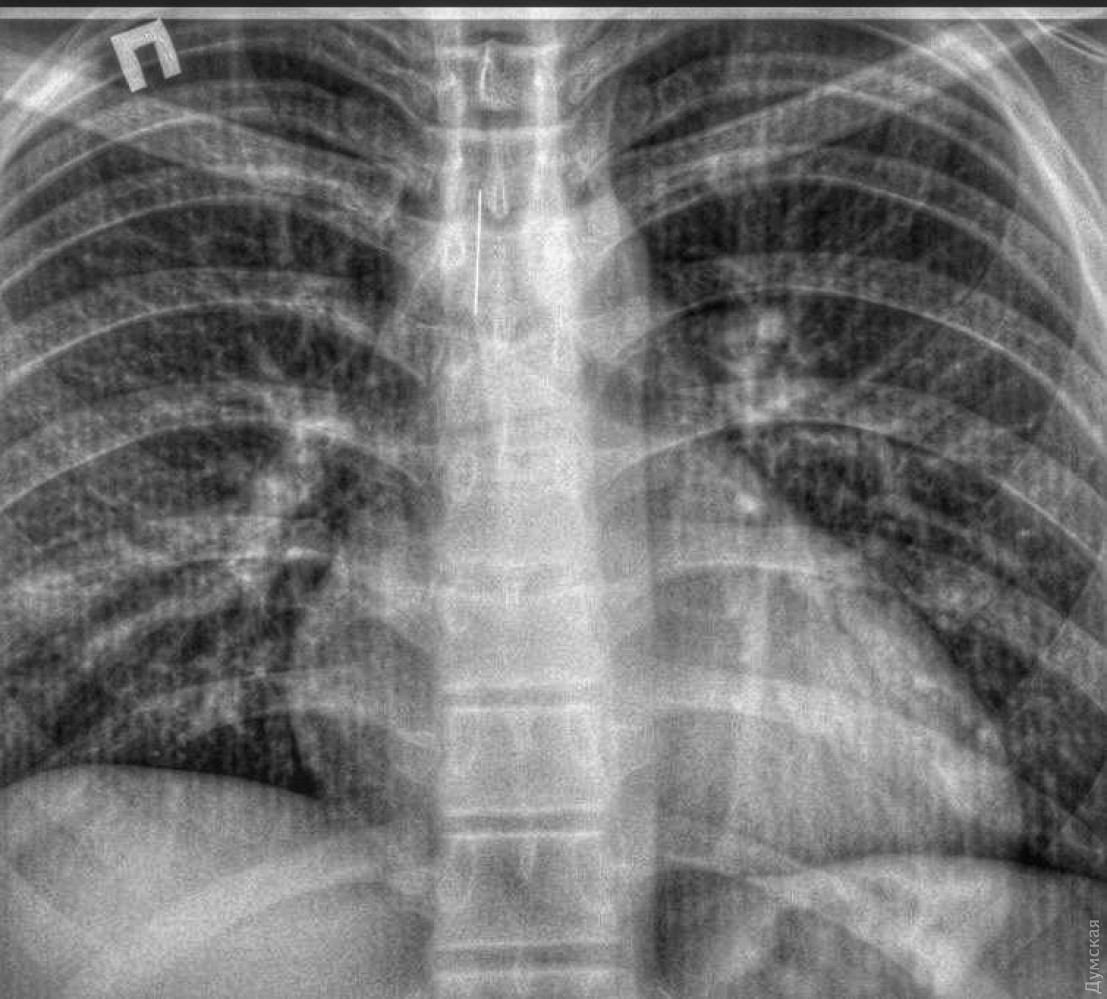

15-річного юнака зі стороннім тілом в трахеї шпиталізували 2 лютого, пише «Бессарабія INFORM». Він випадково «вдихнув» шпильку, яка застрягла на шляху до легень.

У міськлікарні юнаку одразу ж зробили комп’ютерну томографію та з’ясували, що чужорідне тіло застрягло не у стравоході, а саме в трахеї.

Підлітку під наркозом провели бронхоскопію та дістали чотирисантиметрову голку, яка гострим кінцем встромилася у слизову та нікуди не рухалася. За словами медика, саме завдяки цьому і вдалося запобігти травмуванню.